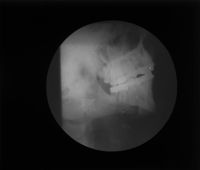

Image[Plaque de projection de radiographies maxillaires.]